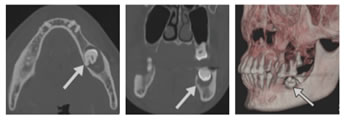

Figure 5: Dentigerous cyst. A–C, Axial (A), coronal (B), and volume-rendering 3D (C) CT views show well-circumscribed unilocular radiolucent lesion (arrows) containing crown of unerupted second molar (tooth 31)

.